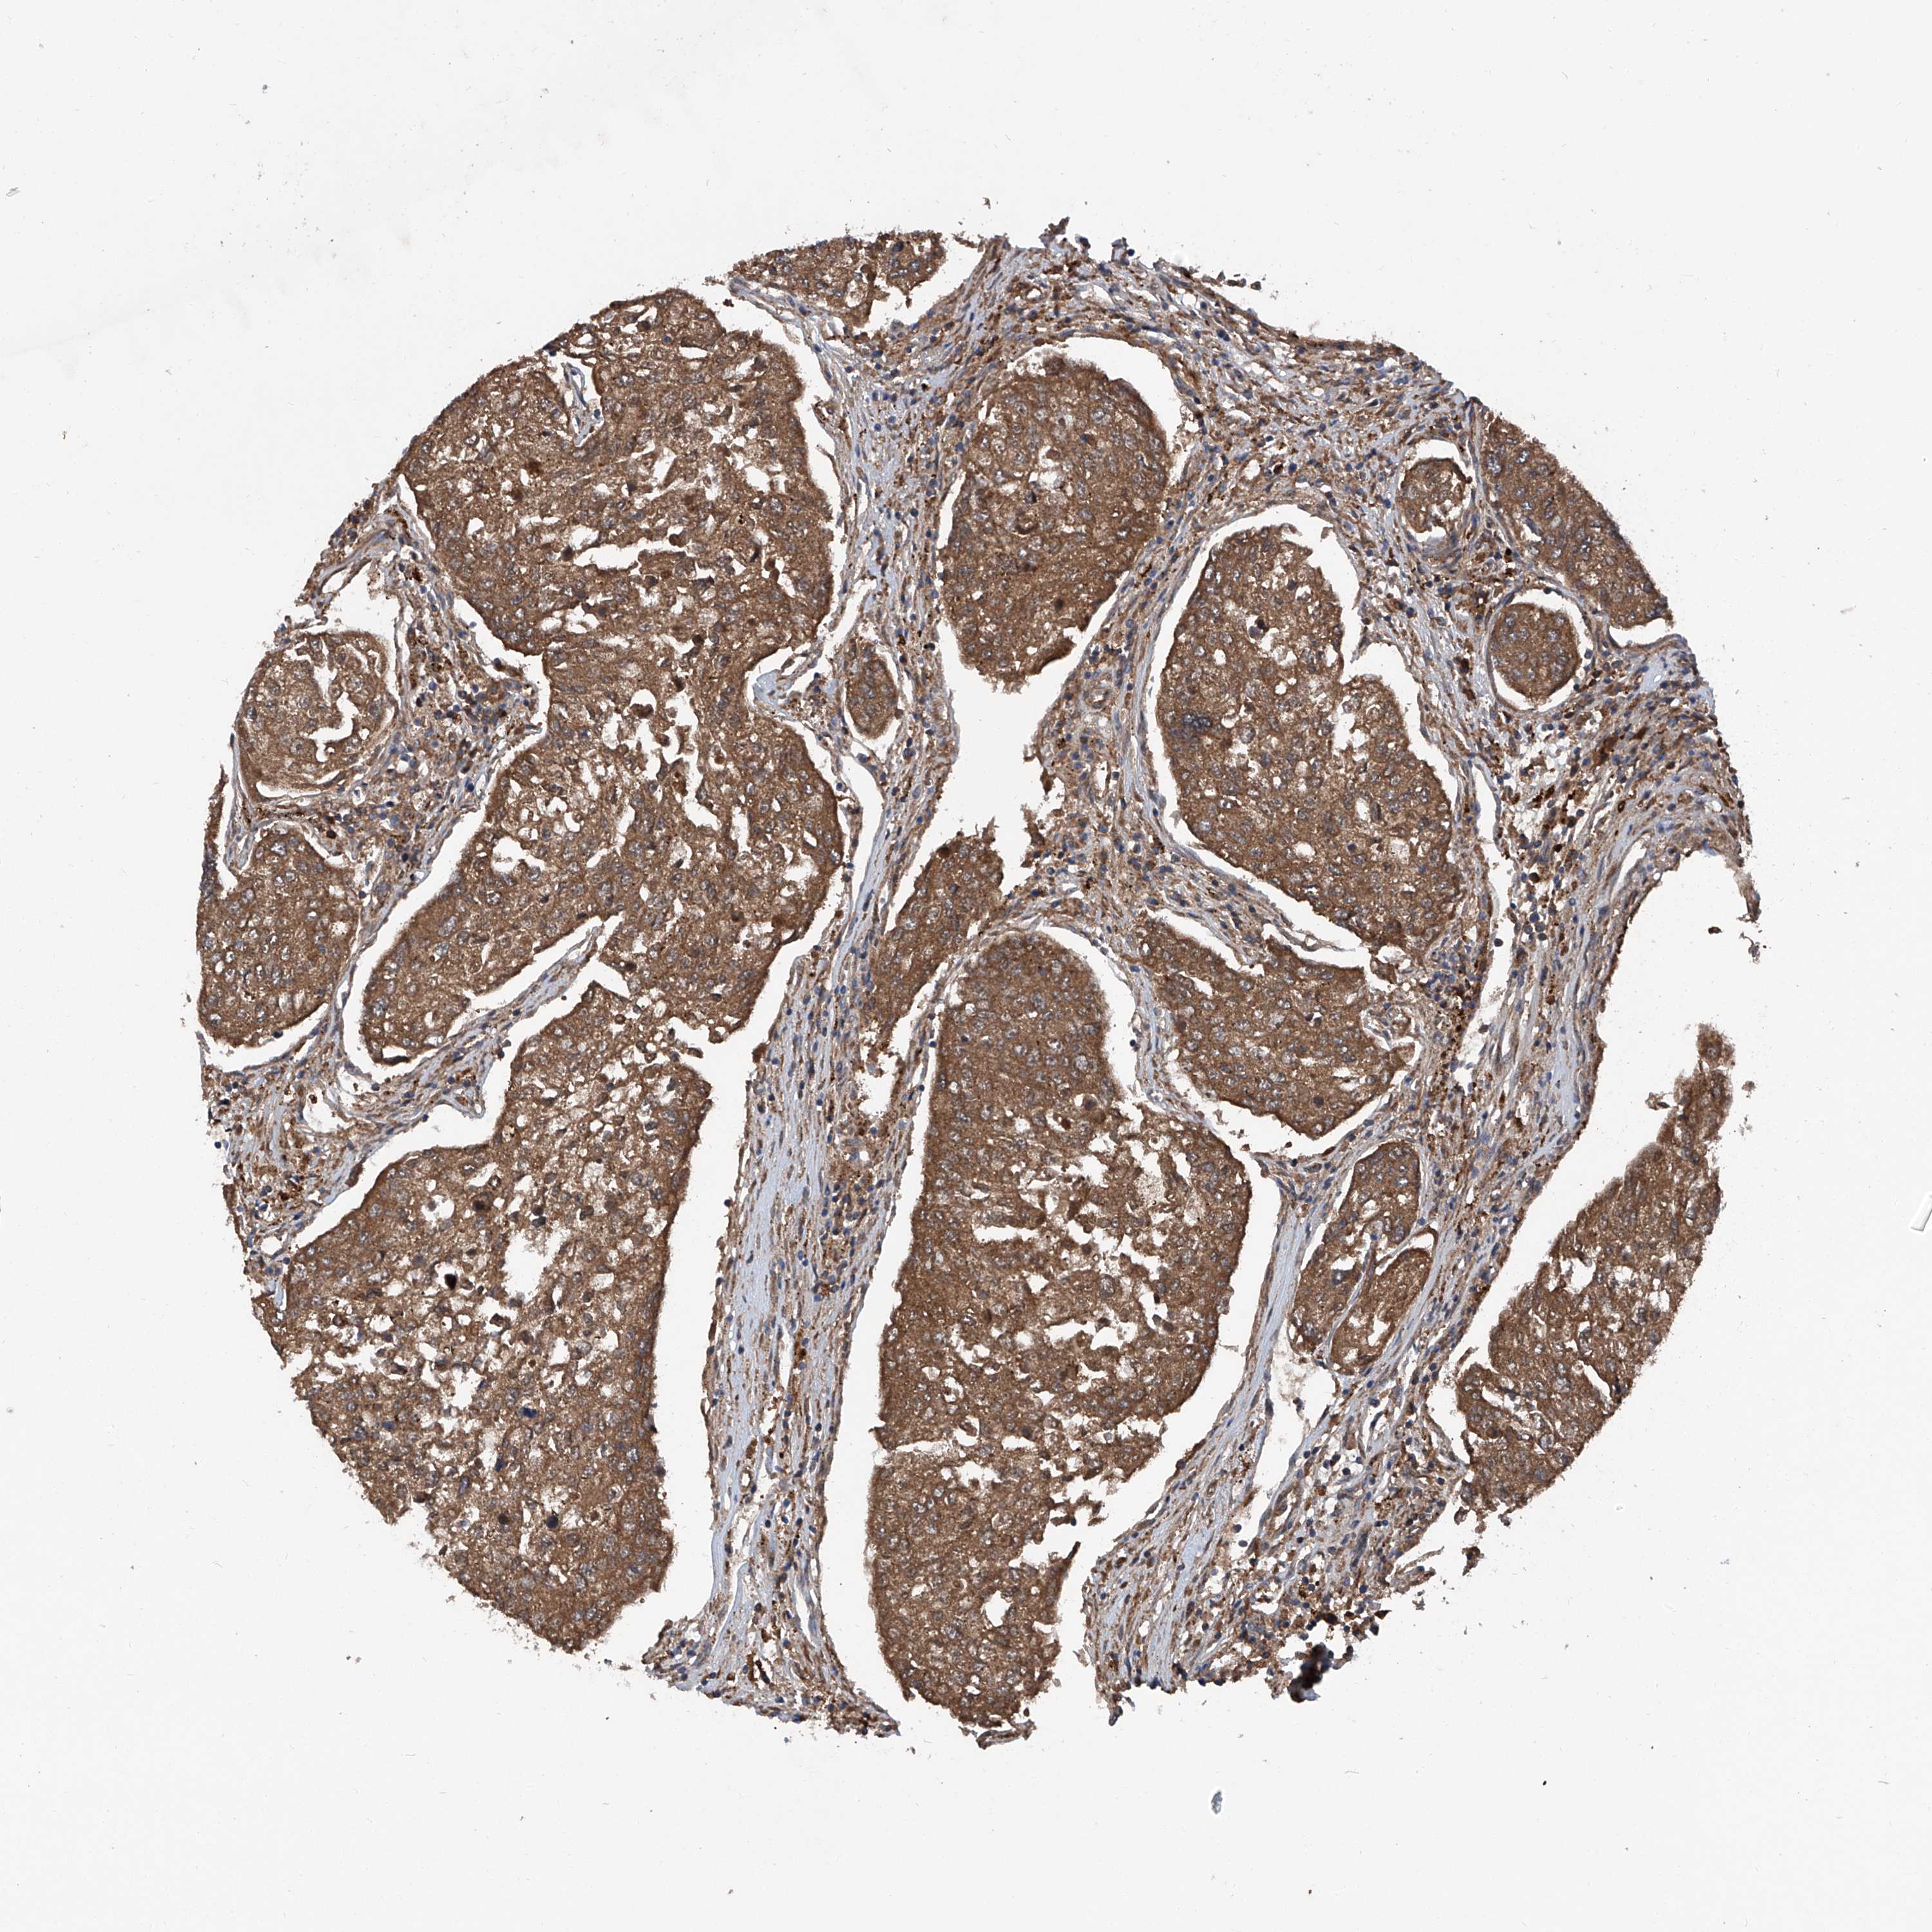

UROTHELIAL CANCER - Protein expressioni

A mouse-over function shows sample information and annotation data. Click on an image to view it in a full screen mode. Samples can be filtered based on level of antibody staining by selecting one or several of the following categories: high, medium, low and not detected. The assay and annotation is described here.

Note that samples used for immunohistochemistry by the Human Protein Atlas do not correspond to samples in the TCGA dataset.

Antibody stainingi

Antibody staining in the annotated cell types in the current human tissue is reported as not detected, low, medium, or high, based on conventional immunohistochemistry profiling in selected tissues. This score is based on the combination of the staining intensity and fraction of stained cells.

Each image is clickable and will lead to virtual microscopy that enables deeper exploration of all samples and also displays staining intensity scores, fraction scores and subcellular localization as well as patient and tissue information for each sample.

Antibody HPA031608

Antibody HPA031609

Antibody HPA031610

Staining

High

Medium

Low

Not detected

Intensity

Strong

Moderate

Weak

Negative

Quantity

>75%

75%-25%

<25%

None

Location

Nuclear

Cytoplasmic/membranous

Cytoplasmic/membranous,nuclear

Urothelial carcinoma, Low grade

Urothelial carcinoma, High grade